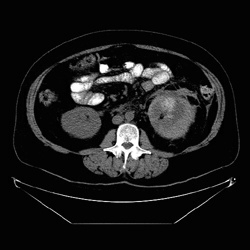

RADIOLOGY: KIDNEY: Case# 33040: RENAL LACERATION W/ PERINEPHRIC HEMATOMA. The patient is a fifty-one year old diabetic with left lower quadrant pain. No history of trauma. 1) Left subcapsular hematoma without evidence of infection. Although no focal parenchymal lesion is identified, this cannot be ruled out as a source of the bleeding.